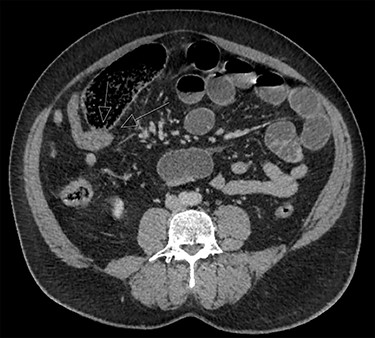

Case 2 is a 56-year-old male, with a virgin abdomen, who had 2 days of crampy abdominal pain, vomiting and obstipation. He was haemodynamically normal and afebrile. He had a distended abdomen with generalized tenderness. Blood tests showed an elevated lactate of 3 and WCC of 11.7 × 109. CT demonstrated distal SBO, with distension of small bowel up to 6 cm (Fig. 3). He underwent a diagnostic laparoscopy with an identification of MD at the transition point, subsequently exteriorized through a mini-laparotomy (Fig. 2). The apex of the MD was tethered to the mesentery through a band containing the diverticular blood supply. Small bowel resection and anastomosis was performed. Histopathology showed MD with acute inflammation, haemorrhage and necrosis, and no ectopic tissue.

In both cases, diagnostic laparoscopy was used to establish and treat the cause of SBO. Unlike cases described in the literature where a specific mechanism is associated with MD causing obstruction, in the two cases we present, the exact mechanism was not directly observed. In case 1, the enteric contents were quite thickened; the possibility of an enterolith could not be excluded, although this was not demonstrated on CT scan. The microscopic diagnosis was also not remarkable, and therefore, the sequence of events leading to obstruction with the transition point is unclear. In the second case, it appeared that a band or adhesions caused tethering of the apex of the MD to the ileal mesentery, which served as the site of the transition point. There was inflammation noted on histopathology; therefore, it is likely that this contributed to the obstruction, although this could be a secondary phenomenon if the adhesions caused volvulus leading to obstruction, as described in another case [8].